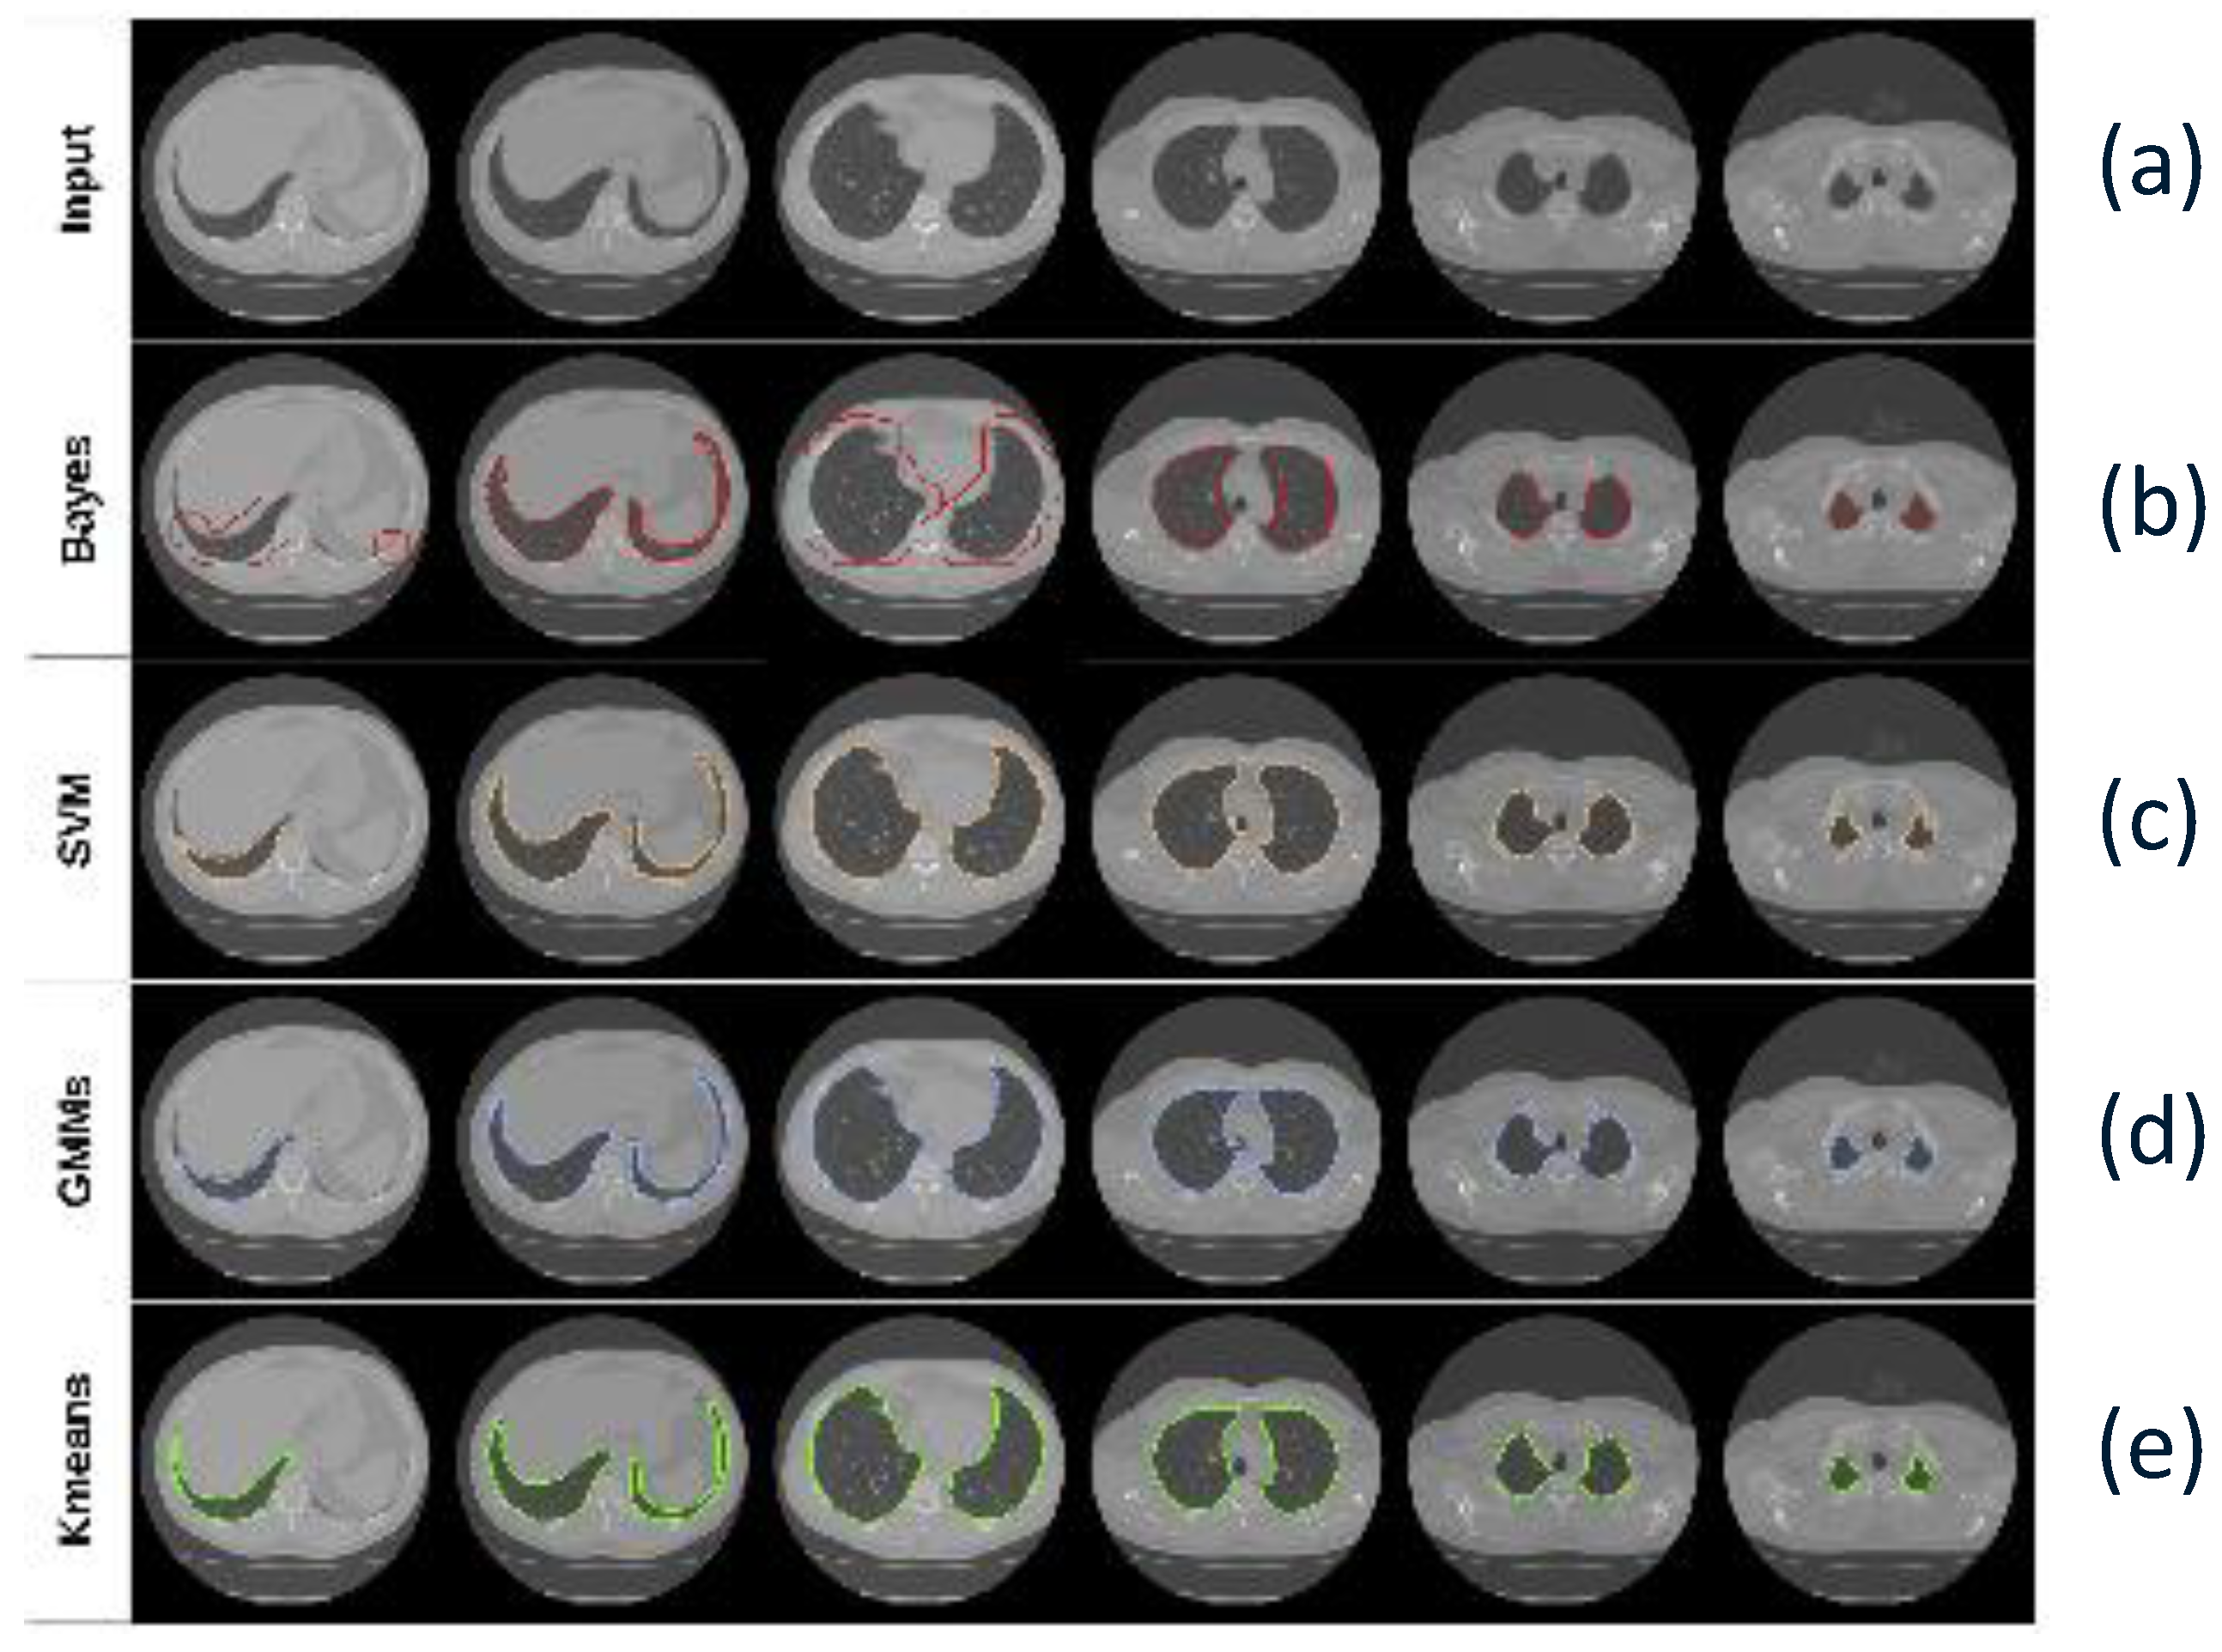

5. Lung Segmentation

6.1. Traditional Methods

7.1. Traditional Methods